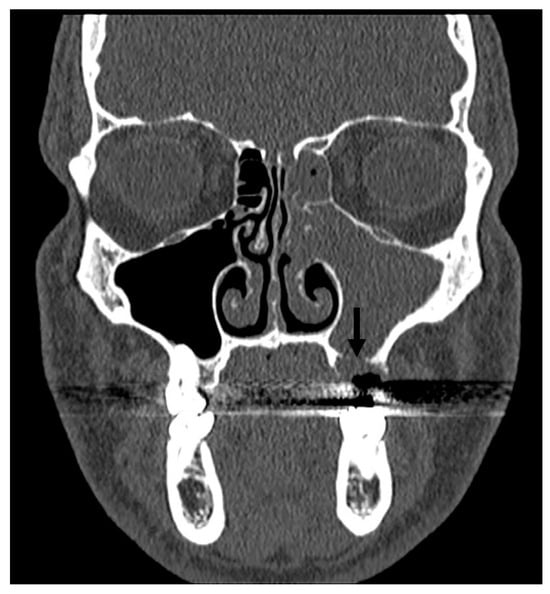

- NSD and nasal spurs can lead to lateral narrowing of the middle turbinate and compression of the middle meatus, resulting in impaired ventilation and facial pain. Additionally, a septal spur may compress the inferior turbinate, which is innervated by branches of the maxillary nerve, causing intermittent pain that varies with the degree of turbinate hypertrophy.